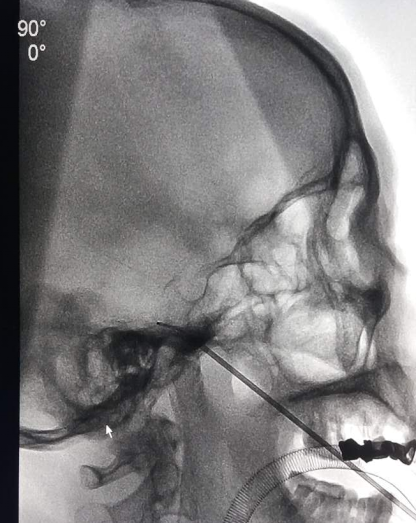

微创解决方案:PBC的创新之处三叉神经球囊压迫术是一种前沿的微创治疗手段,它通过经皮途径,在影像引导下,精确地将一个微小球囊置入三叉神经的半月节区域。随后,球囊被充盈以物理性压迫神经纤维,阻断痛觉传导,而保留触觉功能,实现疼痛的有效缓解。此方法避免了热凝等技术可能带来的神经损伤,更显温和与精准。